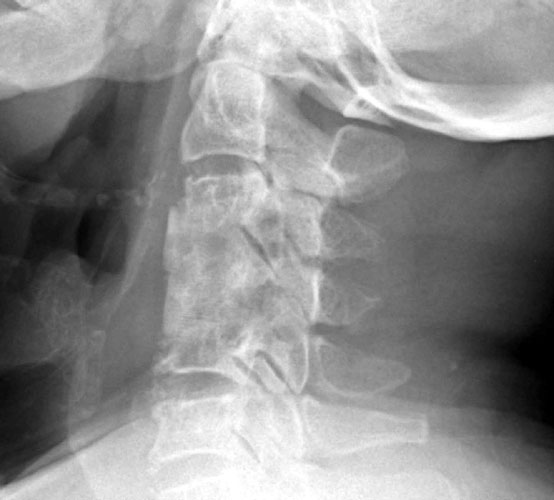

| Lateral flexion and extension views obtained five months after

surgery obtained for surveillance. Note postsurgical changes of anterior fusion

of C3 - C5, however the fusion is not solid at C4 - 5. Movement is detected on

the flexion and extension views at the level of the graft itself. |